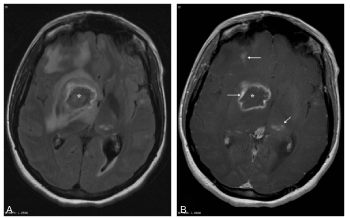

Des abcès multiples (noyaux gris, sous-corticaux) chez un patient VIH+ doivent faire évoquer en priorité une toxoplasmose cérébrale et débuter un traitement antitoxoplasmique (figure 49.2).

Fig. 49.2. Toxoplasmose cérébrale chez un patient VIH+. IRM cérébrale.

Coupe axiale pondérée en T2/FLAIR (A) et en T1 après injection (B) : présence de plusieurs lésions en hypersignal en T2, prenant le contraste (flèches) et entourées d’un œdème. La plus volumineuse (∗) touche les noyaux gris. Ces lésions correspondent à des abcès intracérébraux à toxoplasme.

Source : CERF, CNEBMN, 2022.